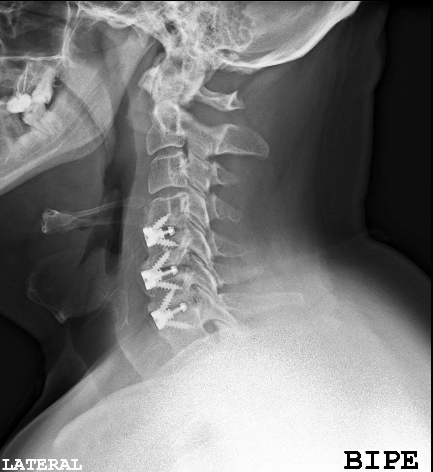

El resultado de la RM cervical planteaba dudas si era necesario o mandatorio realizar una descompresión posterior complementaria. Sin embargo, los parámetros clínicos no sugerían una compresión medular: la evolución lenta a la mejoría de su paresia, la ausencia de progresión de su mielopatía y la ausencia de dolor resultaron determinantes para que se adoptara una actitud conservadora. El paciente fue dado de alta (en plena pandemia de covid) y la evolución fue buena a pesar de que no pudo completar la rehabilitación. Se realizó nueva RM y RX cervical a los seis meses que resultó mucho más concluyente.

A los seis meses de evolución, el paciente sigue pendiente de rehabilitación, ha mejorado su inestabilidad postural y en la marcha aunque persiste la paresia C7 (agravada respecto a preoperatorio, con EMG y registros MNIO con radiculopatía crónica severa).